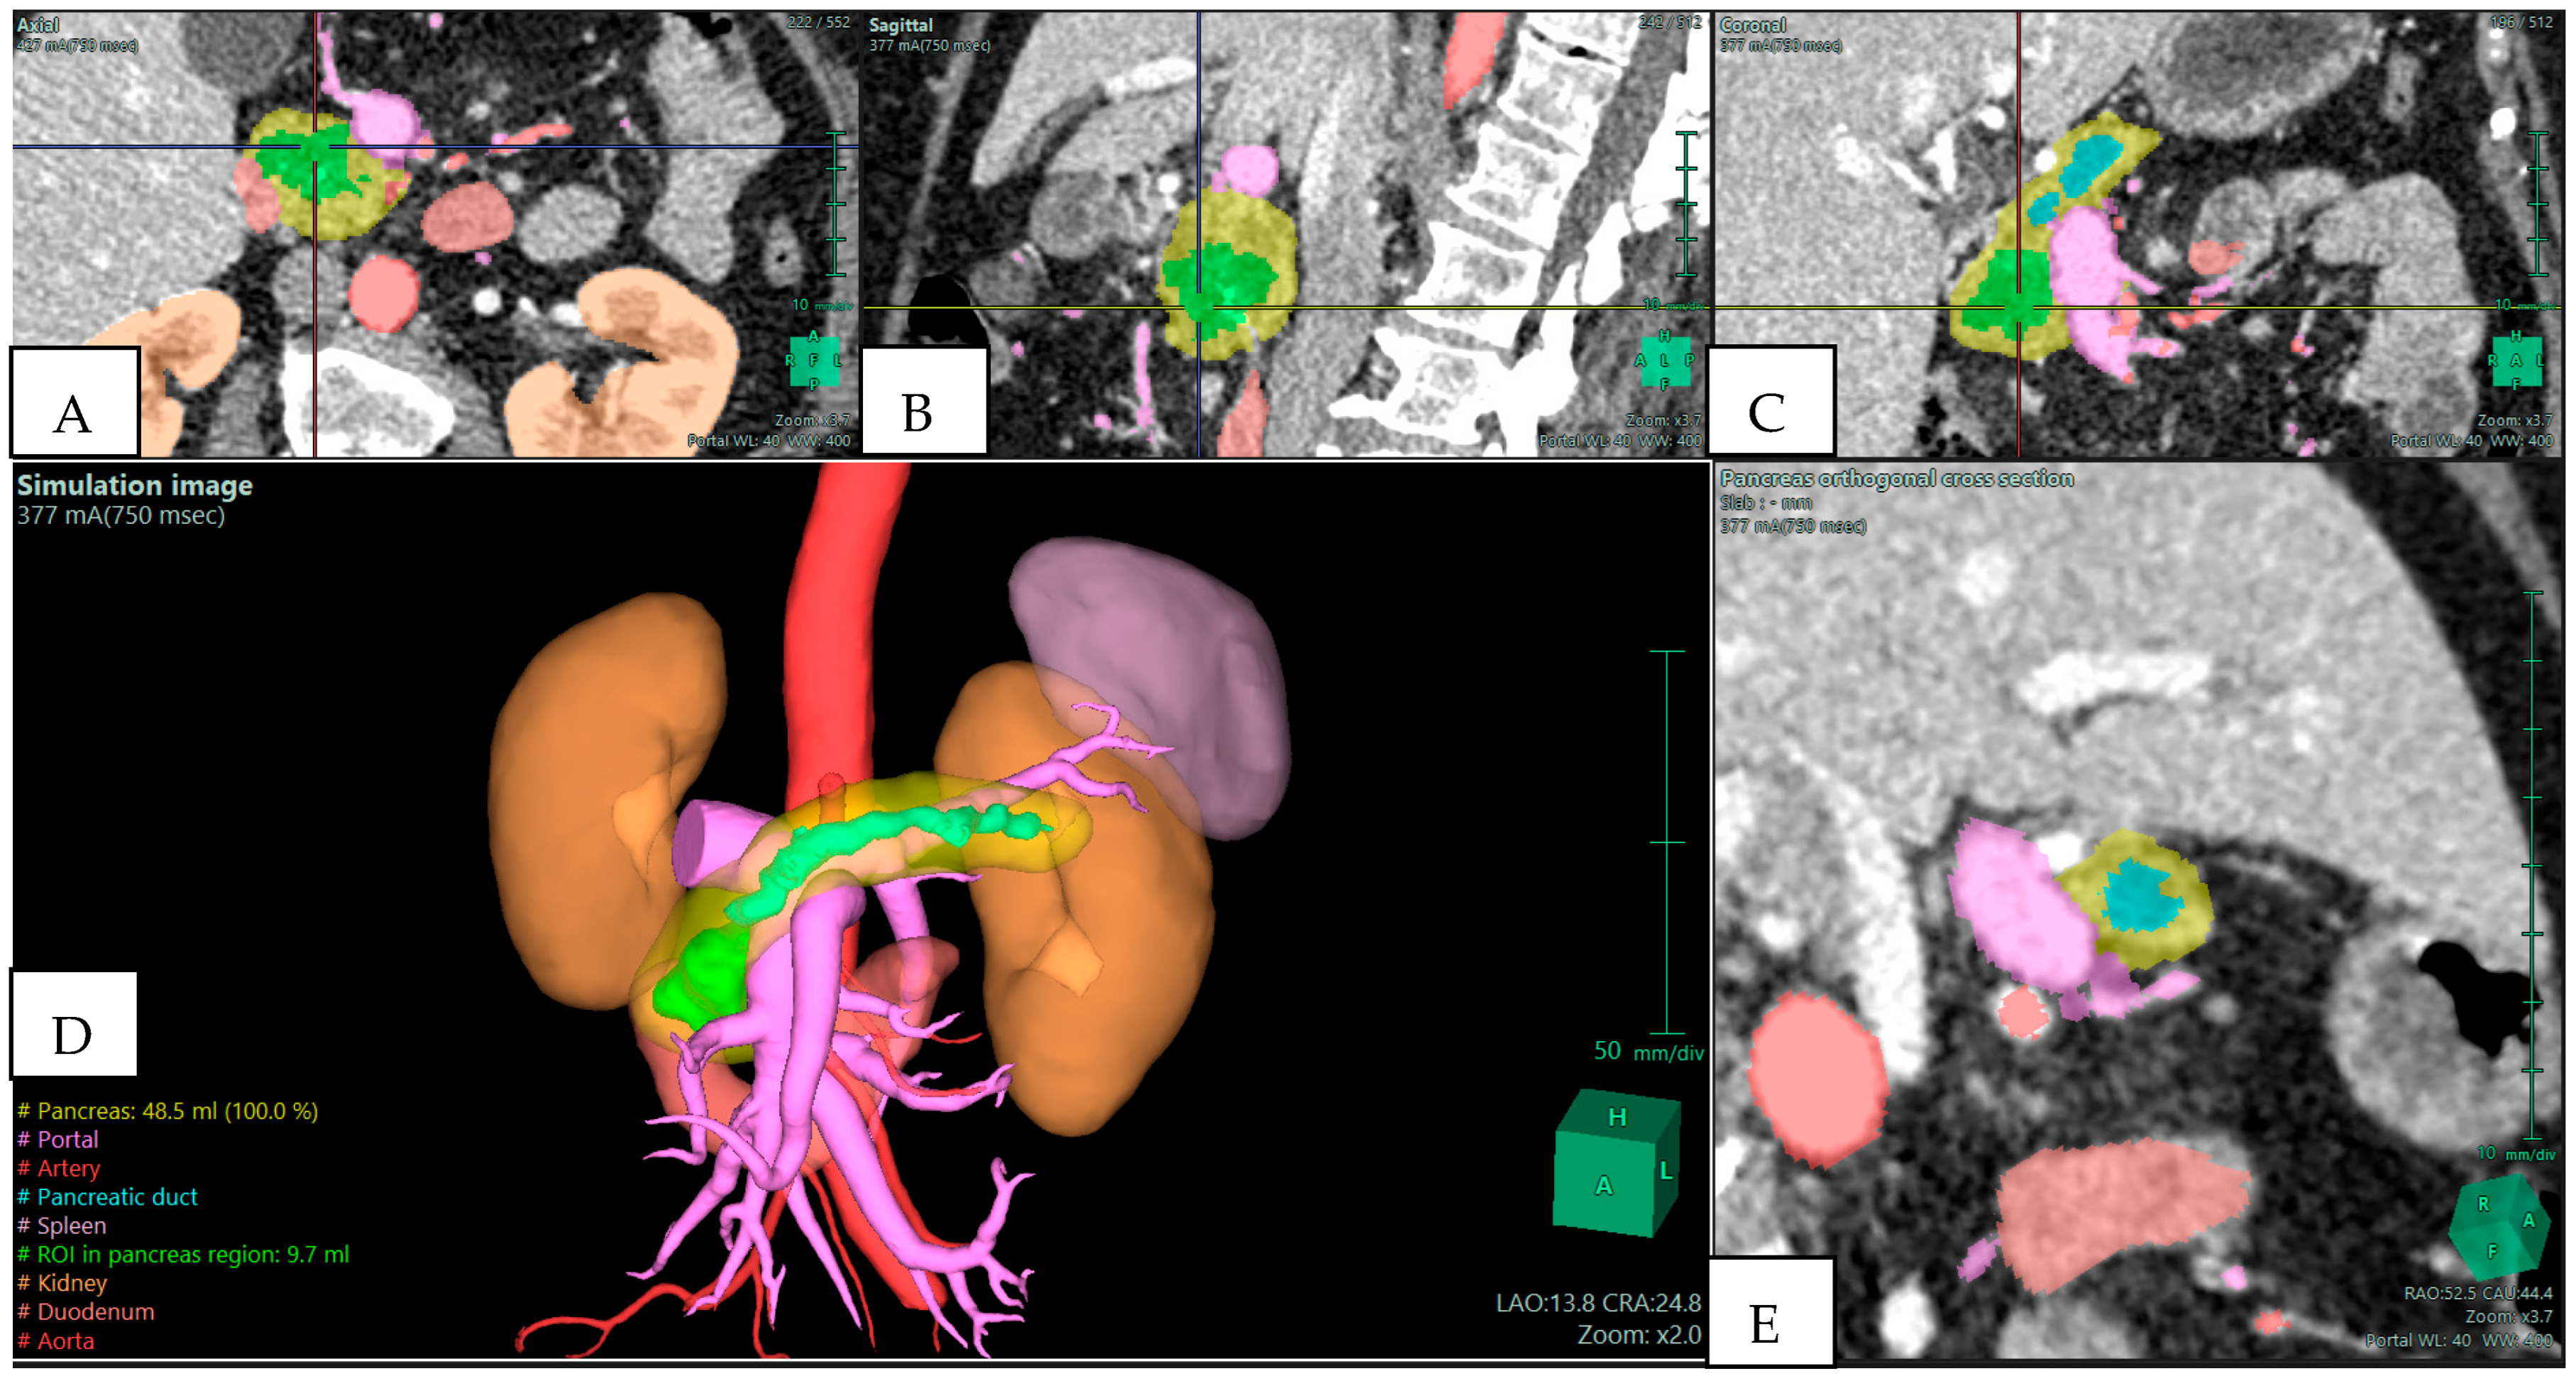

The strongest argument for integrating 3D reconstruction into preoperative planning is its demonstrated ability to alter surgical strategy. Several clinical series have reported changes in operative planning in 20–30% of cases once 3D reconstructions were reviewed. These changes typically involve revised judgments about vascular invasion, resectability, and the extent of resection required. For example, in a study of pancreatoduodenectomies, surgical plans were modified in more than one-fifth of patients after 3D evaluation, with the most frequent adjustments relating to anticipated venous resection or reconstruction [2]. In borderline resectable pancreatic ductal adenocarcinoma (BR-PDAC), where accurate assessment of venous and arterial involvement determines operability, 3D reconstructions have proven particularly useful [6,11]. They allow surgeons to visualize tumor abutment of the SMV–portal vein confluence or encasement of arterial branches in a way that 2D slices cannot, as shown in Figure 1. This not only aids in selecting candidates for upfront surgery versus neoadjuvant therapy but also prepares the surgical team for complex vascular procedures if required.

Figure 1. Preoperative Planning of a Pancreatic Head Adenocarcinoma with Main Duct Intraductal Papillary Mucinous Neoplasm (IPMN) in a 70-year-old Woman. Multiphase CT scan with 3D volume rendering shows the tumor (green) abutting the superior mesenteric vein (SMV)/portal vein (PV) confluence (purple). Images derived from anonymized clinical datasets from our institution. (A) Axial plane; (B) sagittal plane; (C) coronal plane; (D) 3D reconstruction—simulation image; and (E) pancreas orthogonal cross section. Images derived from anonymized clinical datasets from our institution.